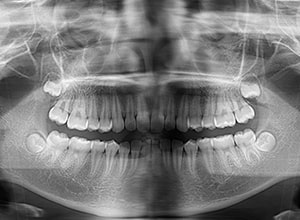

| パノラマ所見 | 右下5は右下6近心傾斜により萌出部位不足が認められた。上下顎8歯胚が確認できた。 |